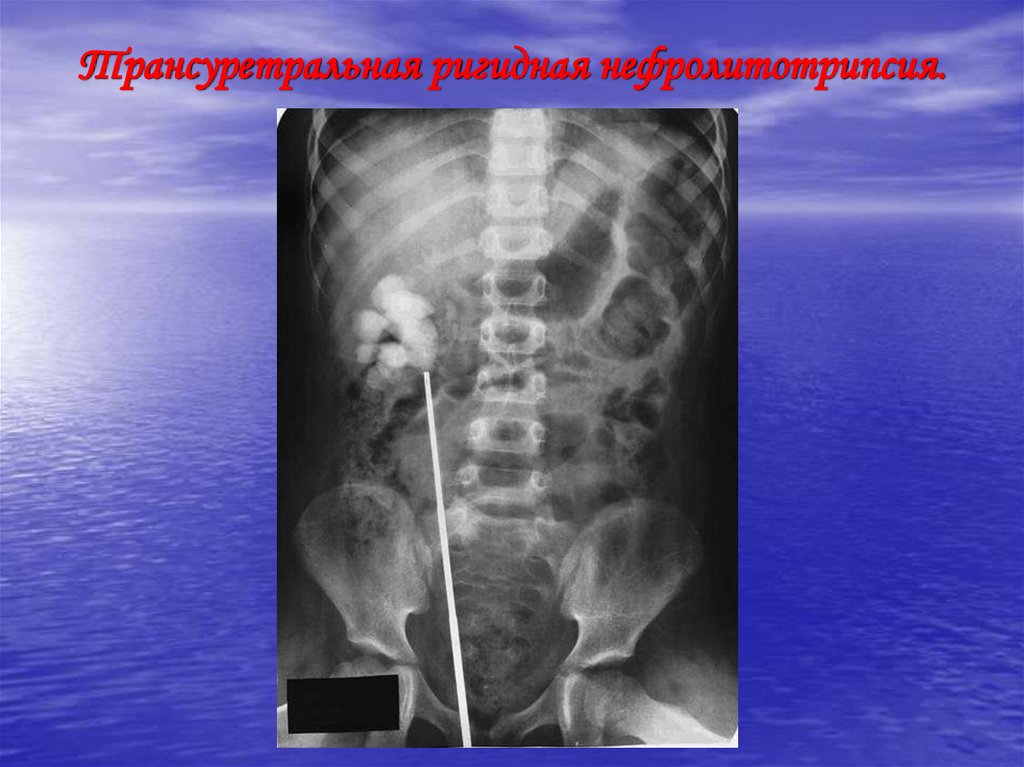

Трансуретральная ригидная нефролитотрипсия.

76. Трансуретральная ригидная нефролитотрипсия.